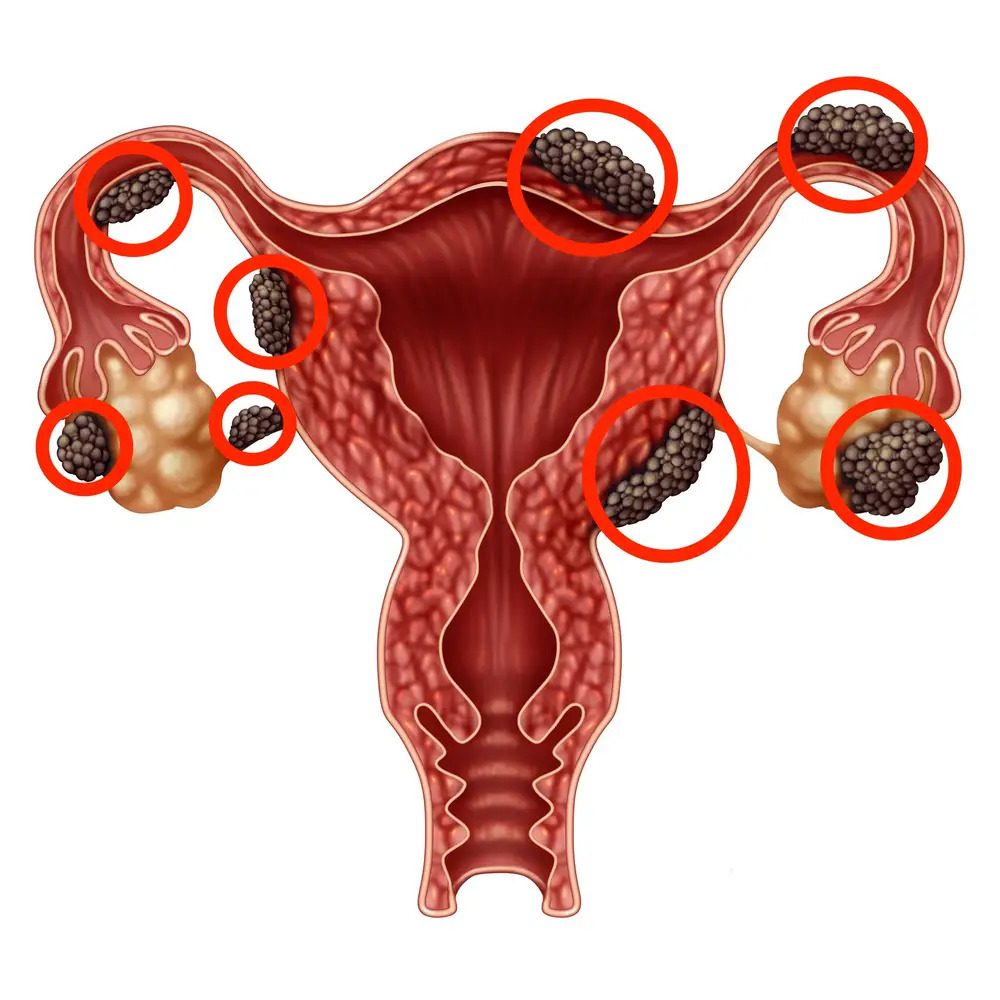

ما هي بطانة الرحم المهاجرة؟

يعرف مرض بطانة الرحم المهاجرة باللغة الإنجليزية باسم (Endometriosis)، وهو عبارة عن حالة طبية تنمو فيها أنسجة مشابهة لبطانة الرحم خارج الرحم، خاصةً في منطقة الحوض، و يعد السبب الدقيق حول مشكلة بطانة الرحم المهاجرة غير معروف حتى الآن، ولكن هناك العديد من النظريات التي توضح السبب الأساسي لحدوث مشكلة بطانة الرحم المهاجرة، ومن أكثر تلك النظريات شيوعًا هو حدوث الحيض الرجعي، حيث يتدفق الدم الذي يحتوي على خلايا بطانة الرحم للخلف عبر قناتي فالوب إلى التجويف البطني، وتوجد بعض العوامل الأخرى المحتملة مثل الوراثة، ونظام المناعة، وبعض العوامل البيئية.

تعاني المرأة المصابة بمرض بطانة الرحم المهاجرة من بعض الأعراض، والتي قد تشتمل على ما يلي:

- آلام وتشنجات أثناء الدورة الشهرية.

- الدورة الشهرية غير منتظمة.

- ألم أثناء أو بعد العلاقة الحميمة.

- ألم أسفل البطن، أو الظهر.

- صعوبة وتأخر الحمل.

- ألم عند التبول.

- نزيف شديد أثناء فترة الحيض.